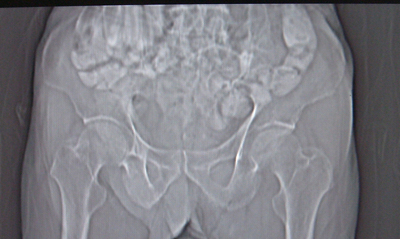

前列腺癌术后10余年,复查有无复发,请指教,图像做得不好,还望包涵

前列腺增大,向上突入膀胱内,结合病史考虑前列腺癌复发可能。

图像太小,左侧膀胱壁似见不规则突起,前列腺突入膀胱,建议膀胱镜检查及前列腺增强检查。